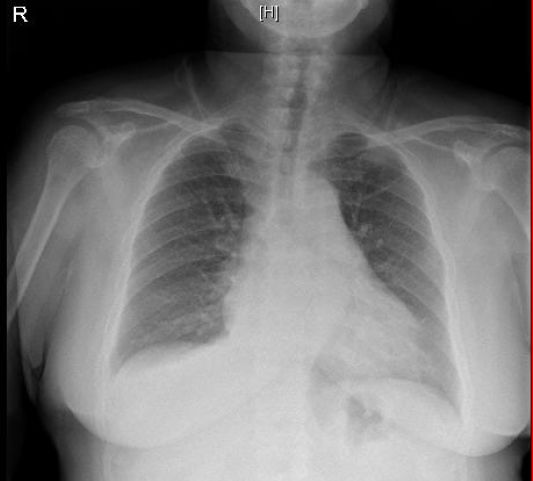

患者治疗3天后复查胸片显示:心影增大、肺淤血等情况较之前有好转;右侧胸腔积液明显减少(见图11)。可见利尿剂的治疗有显著疗效,也可能与一过性膈神经损伤有关。

图11:复查胸片提示右侧胸腔积液明显减少(2018-09-29)